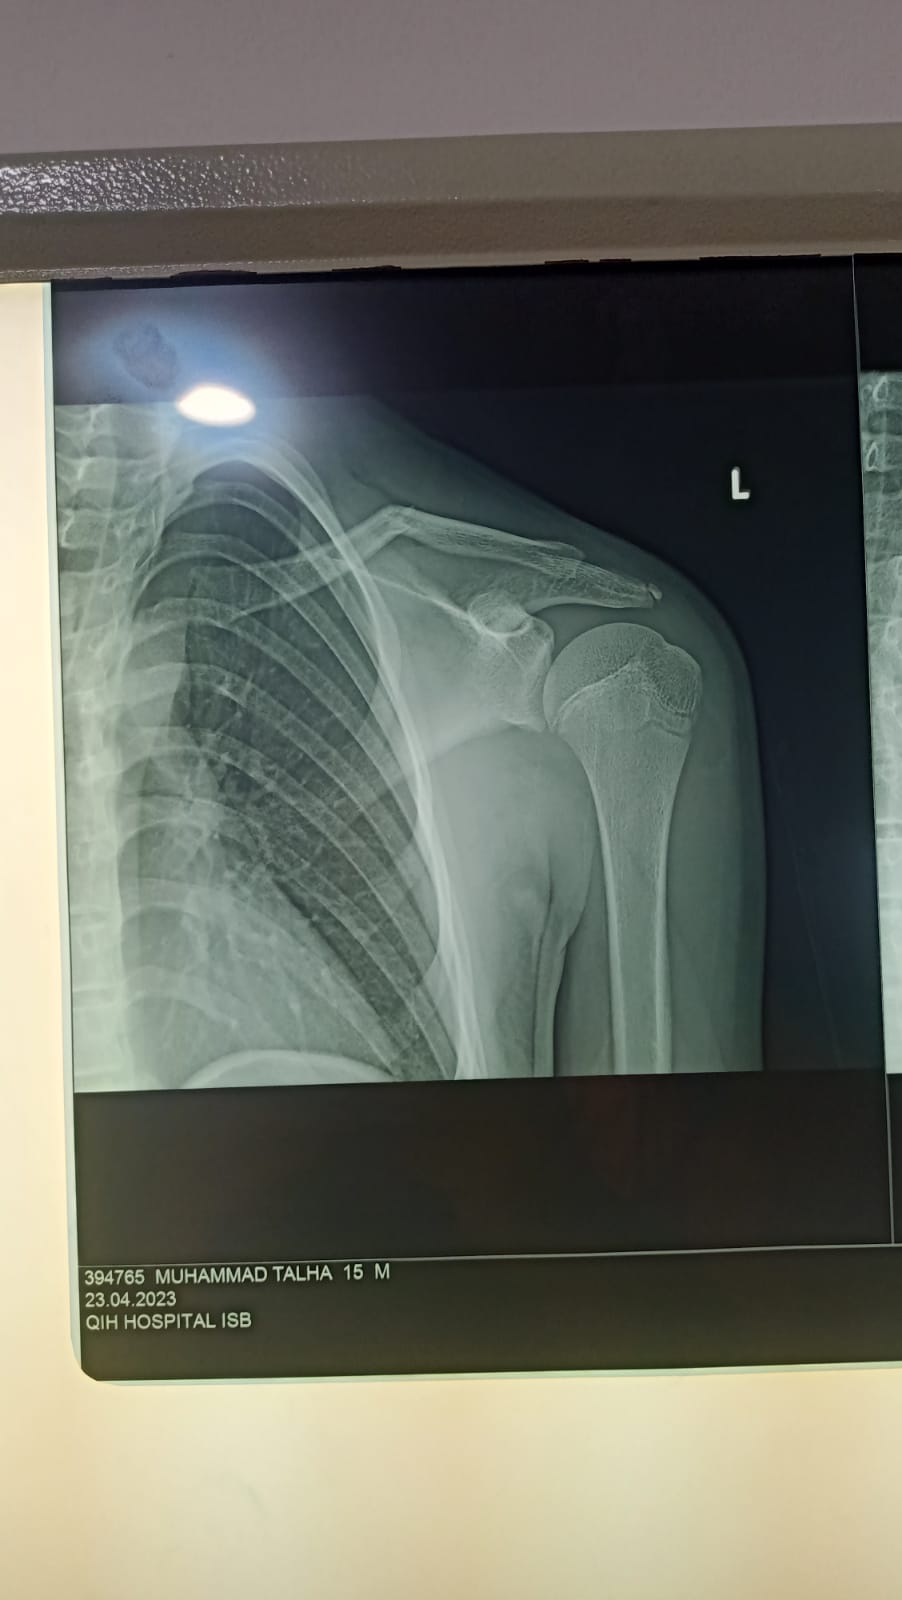

16 yr boy had bike accident 4 days ago,this is his x ray .he is having sling.. now he is feeling sweling on the guide..

his clevicle ( also known as beauty bone ) is fractured . kindly consult some orthopedic for further management .

green stick /undisplaced collar bone(clevicle) ,nothing to worry much,

needs to see pt for other injury,

this fracture will heal on it own,

nothing to do special except to apply a sling/collar and cuff bandage if available to avoid further deformity or displacement....

painkillers like paracetamol and calcium supplements should b given make him pain free and achieve good healing of the bone

If there is skin tenting then it should be operated.042-32591427, kindly contact for further evaluation

Keep in sling for four weeks. Seedling will be reduced with time 2-3 weeks.

He only needs sling for comfort. Bone will heal well. Swelling will go in 6 months. No need for operation- start moving shoulder next week

press clavicle down for reductions and cp bandage 8 of figer plus poly sling for 3 to 4 weeks after that cheek x rays plus start physiotherapy no surgery required